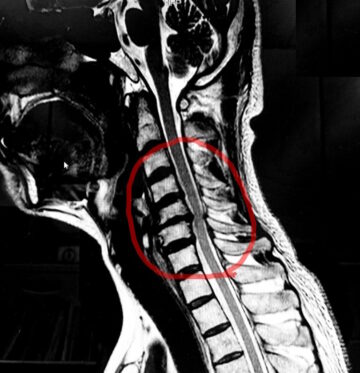

当時は大きな症状はなかったものの、整形外科でのMRI検査により「頚椎症」と診断され、首の骨の並びや間隔が狭くなり、神経が圧迫されていると説明を受けていました。

(これはご本人のMRI画像です。赤丸の部分に変性が生じ、神経を圧迫している様がわかります。)